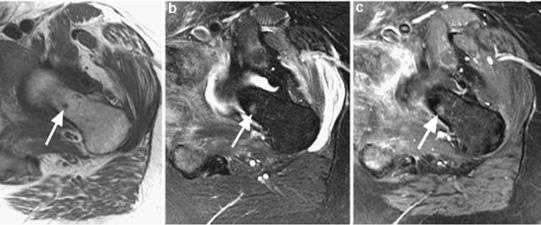

Инвазивная уротелиальная карцинома.

а)Т2-tra б) Т1-sag в)Т2-диффузия (DW)

Мужчина, 72 года. В заднее-левых отделах мочевого пузыря визуализирвется объемное образование (уротелиальная карцинома), стадия 3b.

(а) Аксиальное T2-взвешенное изображение показывает больших размеров опухоль с инвазией мышечной стенки и развитием гидроуретера (стрелка). Видна инвазия мышечного слоя, но достовено судисть о паравезикальном распространении невозможно.

(б) Динамическое контрастирование на скане, проходящем перпендикулярно к основанию опухоли выявляет тотальное поражение стенки пузыря, нечеткость заднего контура опухоли.

(в) Поперечное диффузионно-взвешенное изображение демонстрирует большую опухоль с признаками трансмурального роста и инвазии в паравезикальную клетчатку (стрелка).